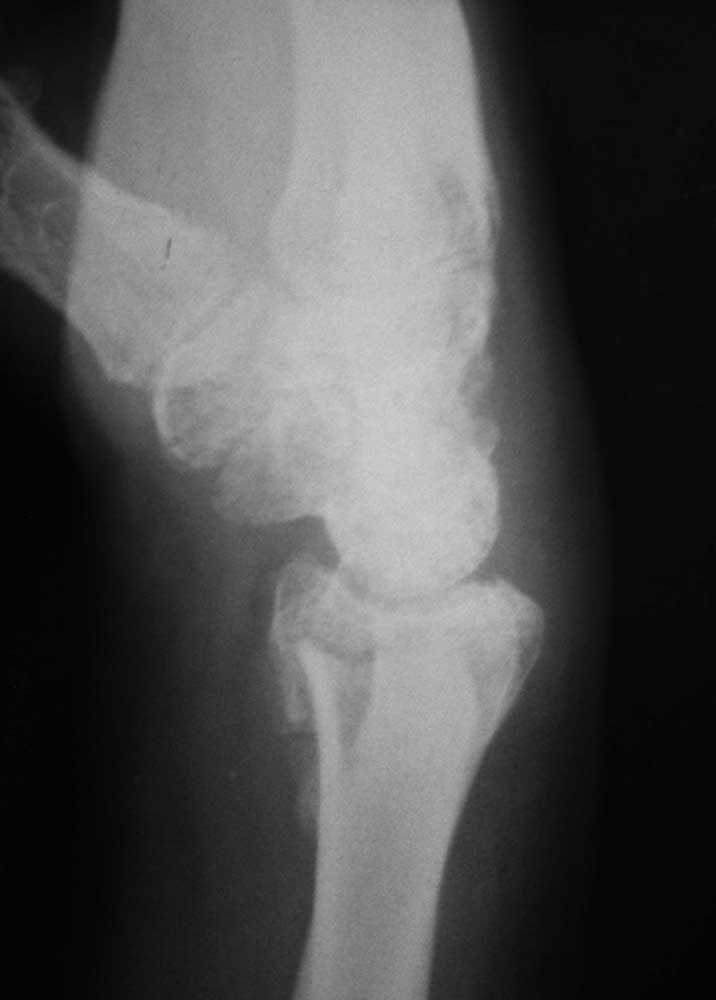

То же самое, только в профиль